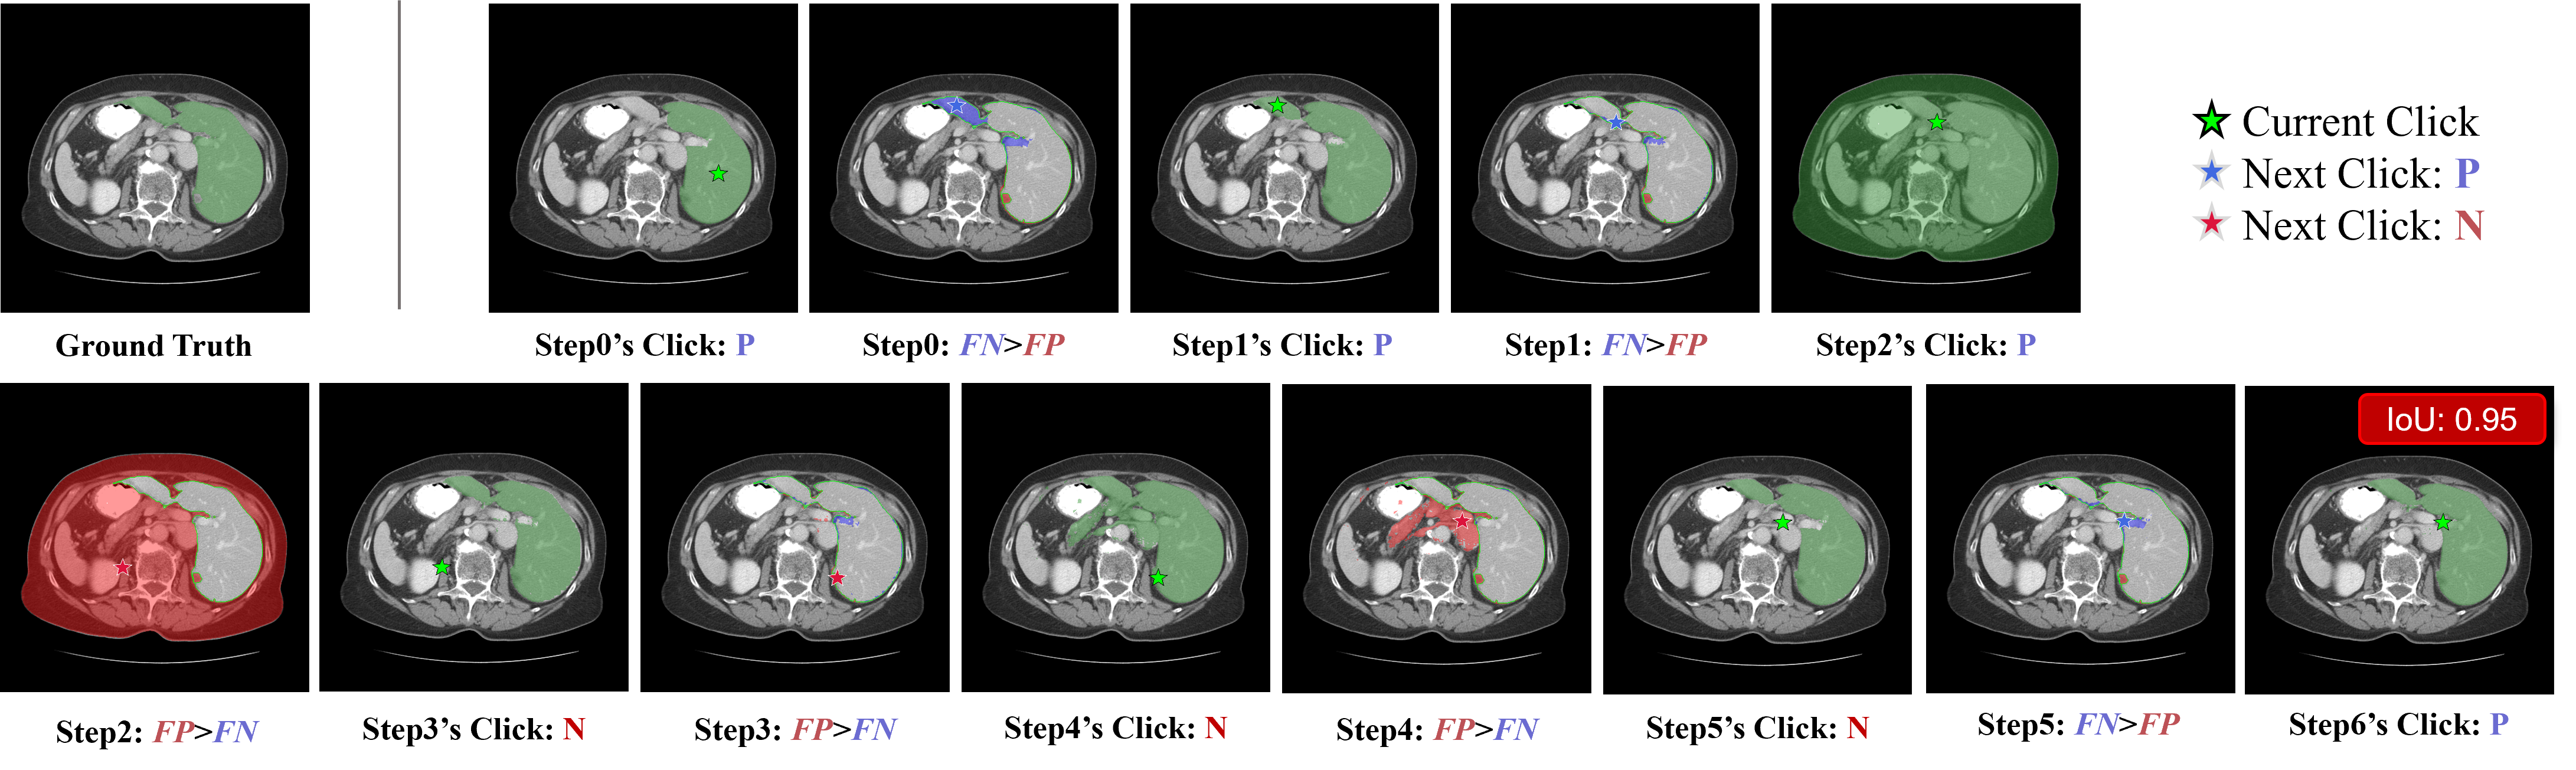

Refer to caption

Figure 5: An illustrative example of the automated trajectory generation process for liver segmentation. The algorithm progressively refines the predicted mask through iterative interactions.

For each iteration (e.g., Step 0), two visualization panels are presented: (1) The

first image displays the current segmentation state, showing the predicted mask (green translucent overlay) generated by the current click (marked by a green star). (2) The second image illustrates the error analysis against the Ground Truth (delineated by a green outline). The differences are visualized as blue translucent regions for False Negatives (FN, under-segmentation) and red translucent regions for False Positives (FP, over-segmentation). The star in this panel indicates the calculated next action based on the largest error region: a blue star denotes a Positive Click (P) to correct under-segmentation, while a red star denotes a Negative Click (N) to correct over-segmentation.